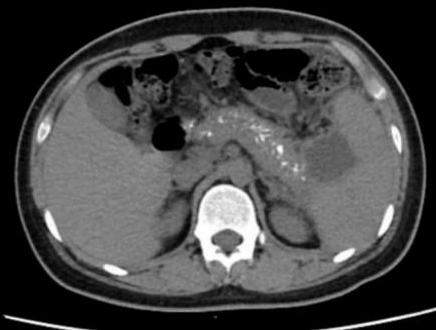

1 资料与方法患者男,17岁,主因“反复腹痛2年,加重伴发热2 d”来诊。患者于2019年起常于进食后出现腹部不适、纳差、腹痛,服用“胃药”对症处理后可好转,此后反复发作,频繁时半月发作一次。2020年9月下旬患者进食油腻食物后出现脐周及左中腹部胀痛,无恶心、呕吐,当地医院腹部CT提示:慢性胰腺炎急性发作,经对症治疗后2~3 d好转,此后每月有类似症状发作一次。2021年1月18日到本院基本外科门诊查胰腺功能,血清淀粉酶73 U/L,脂质624 U/L; 血钙正常; 血脂4项正常; 检查肿瘤指标,CA-125: 46.9 U/mL(升高),余为阴性; 甲状旁腺素正常; 血清IgG四项:IgG3 154 mg/L(降低),IgG4 1 600 mg/L(升高)。腹盆CT示胰腺多发钙化,胰尾囊肿形成(图 1)。1月22日患者进食汤面后出现腹部不适、纳差、乏力。1月24日晨起后出现腹部剧烈疼痛,伴发热,最高37.6℃,无恶心呕吐,无腹泻,于本院急诊就诊查血象正常,超敏C反应蛋白142.15 mg/L,胰腺功能:血清淀粉酶130 U/L, 脂质1 127 U/L。行腹盆CT检查示:胰腺饱满伴多发钙化,胰周脂肪密度稍增高,可见多发索条影,符合慢性胰腺炎改变(图 2)。予厄他培南抗感染及抑酸、补液等支持治疗后症状略好转,于1月26日收入本院急诊留观继续治疗。既往史:早产儿(32周),右桡骨小头骨纤维瘤术后,过敏性哮喘。个人史:否认饮酒史。家族史:父母体健,无其他特殊情况。

| 图 2 患者2021-01-24腹部CT |